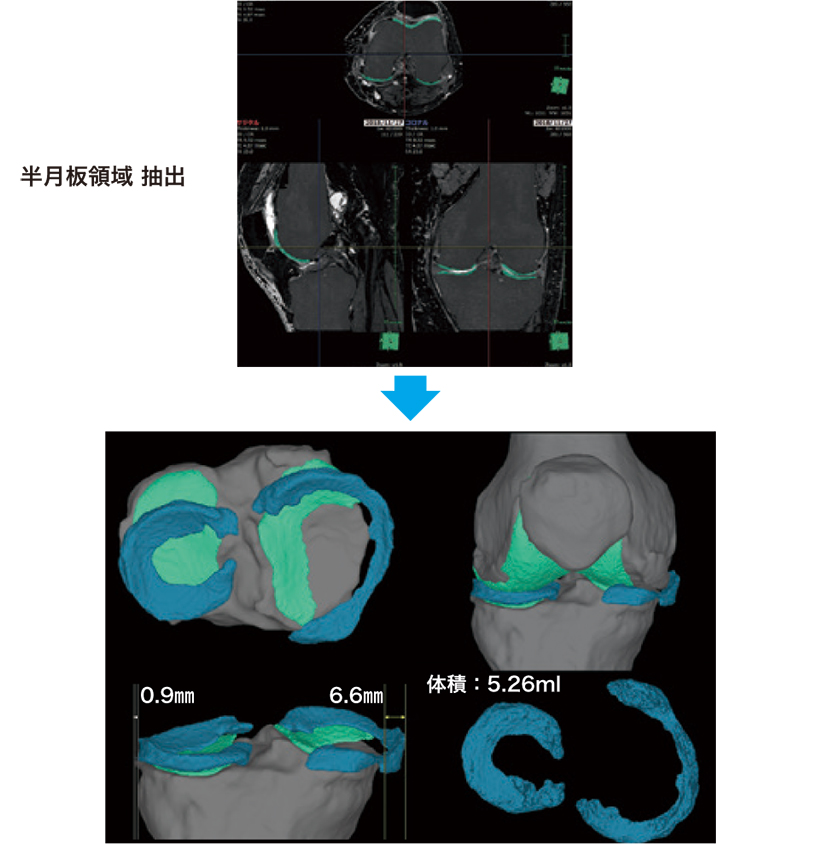

さらに半月板では、3D構成により脛骨関節面との位置関係や逸脱の幅、体積の計測が可能である(図2)。

図2